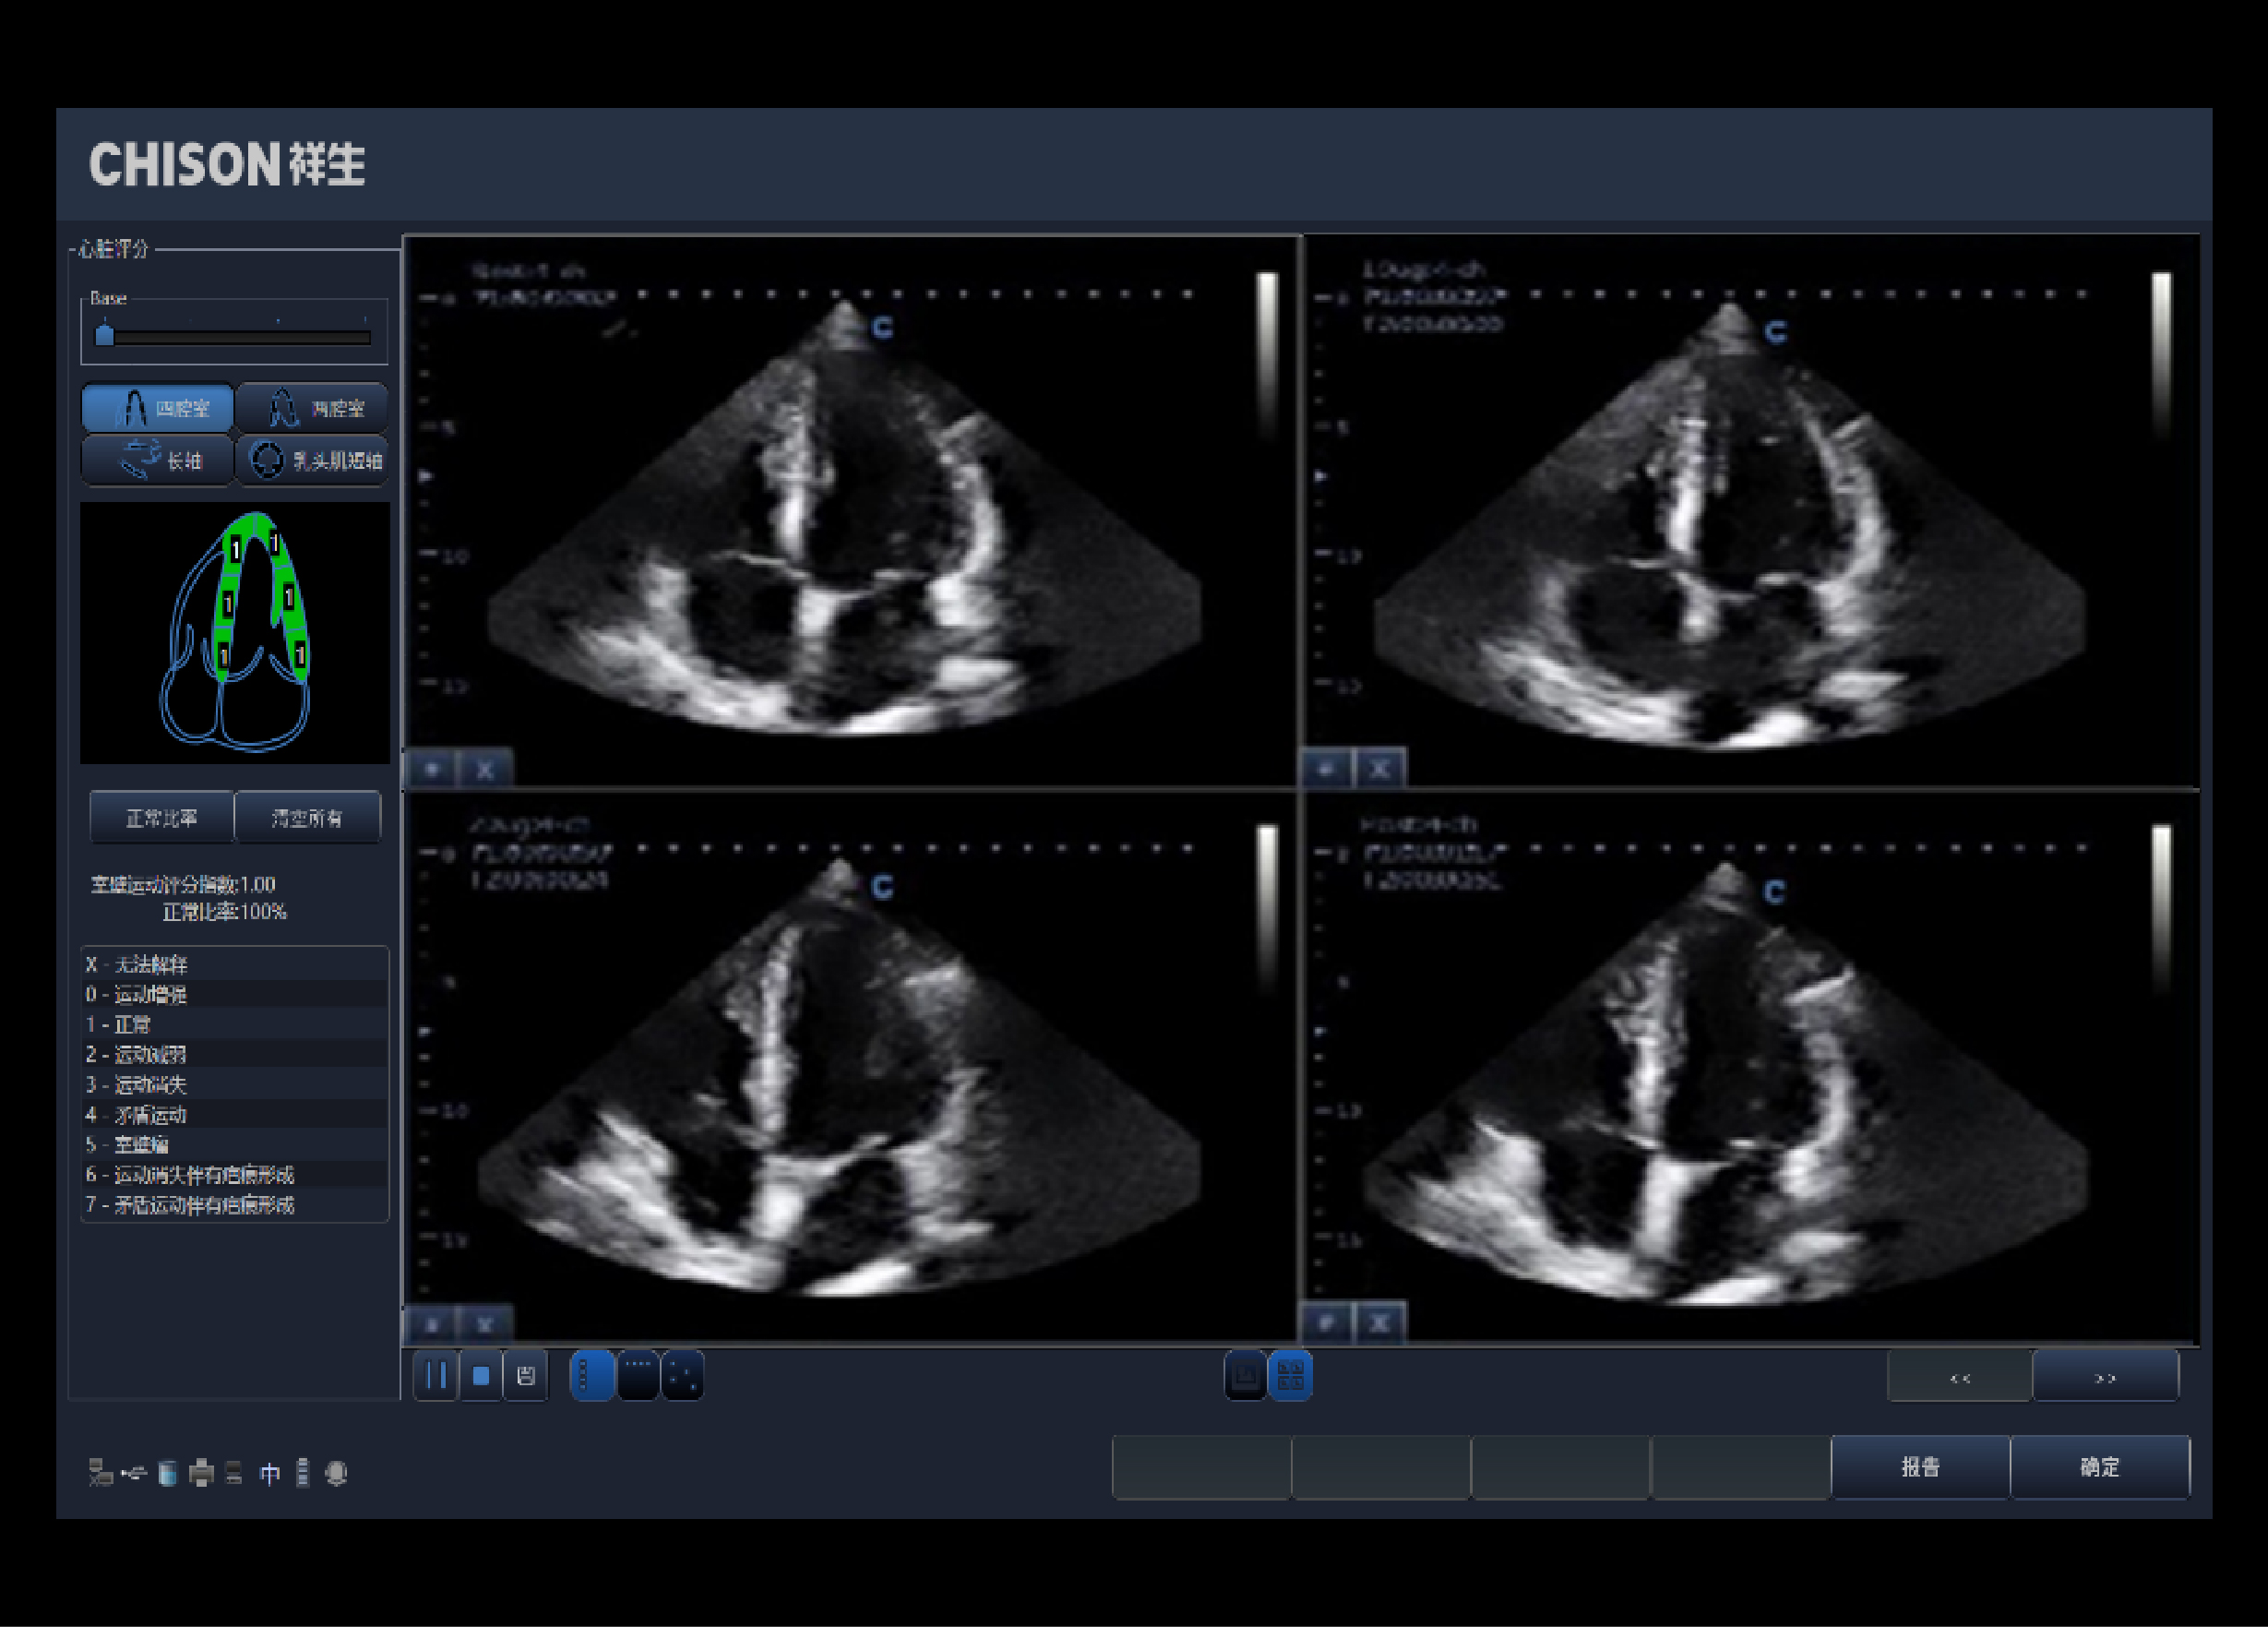

相控阵探头,实时状态下点击触摸屏菜单负荷心超,进入应用。帮助确认或排除冠状动脉疾病的存在。